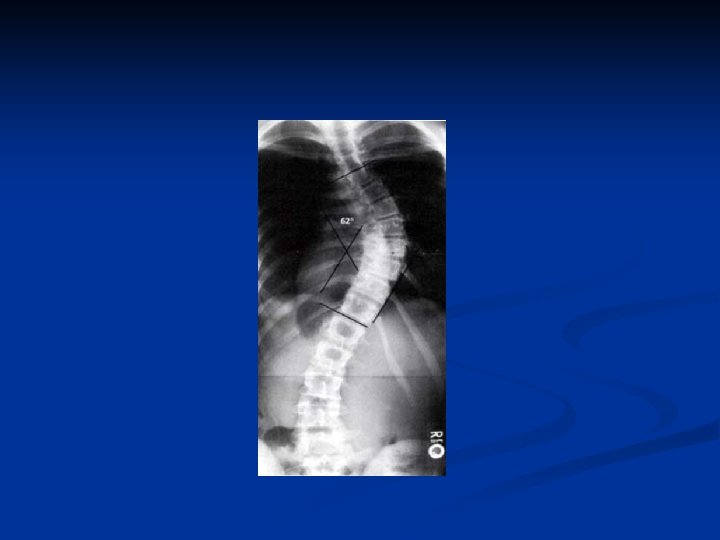

Scoliosis Lateral curve in the spine in AP view

n Diagnosis: n Angle: X-ray n n n Normal Spine (0 degrees) Scoliosis: (> 10 degrees) Complications: (severe scoliosis) n Lung and heart damage: compression of rib cage against heart, lungs n n > 70 degrees Back problems

Measure spinal curvature using Cobb method : - Choose the most tilted verterbrae above & below apex of the curve. - Angle b/t intersecting lines drawn perpendicular to the top of the superior vertebrae and bottom of the inferior vertebrae is the Cobb angle.